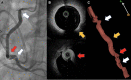

Case summary: The case of a 59-year-old man who underwent conservative mitral valve surgery with tricuspid valve annuloplasty is presented. The early post-operative period was complicated by acute coronary syndrome with inferior persistent ST-segment elevation. A coronary angiogram confirmed critical RCA hazy lesions, raising the suspicion of coronary kinking. To confirm the underlying mechanism for these lesions and determine the best treatment strategy, endocoronary imaging was performed, revealing coronary kinking of the RCA. Based on the persistent acute ischaemia, a long-lasting drug-eluting stent (DES) was implanted in the lower and upper knees of the RCA. After angioplasty, electrocardiography showed regression of the ST-segment elevation. Ten days later, coronary angiography and optical coherence tomography showed good results. The patient recovered from his myocardial infarction.

Discussion: Only a few reports describe the use of endocoronary imaging for diagnosing coronary artery injury after tricuspid annuloplasty. The variety of lesion types that could underlie a single post-operative myocardial infarction makes endocoronary imaging a relevant technique to guide management strategy and optimize DES implantation.